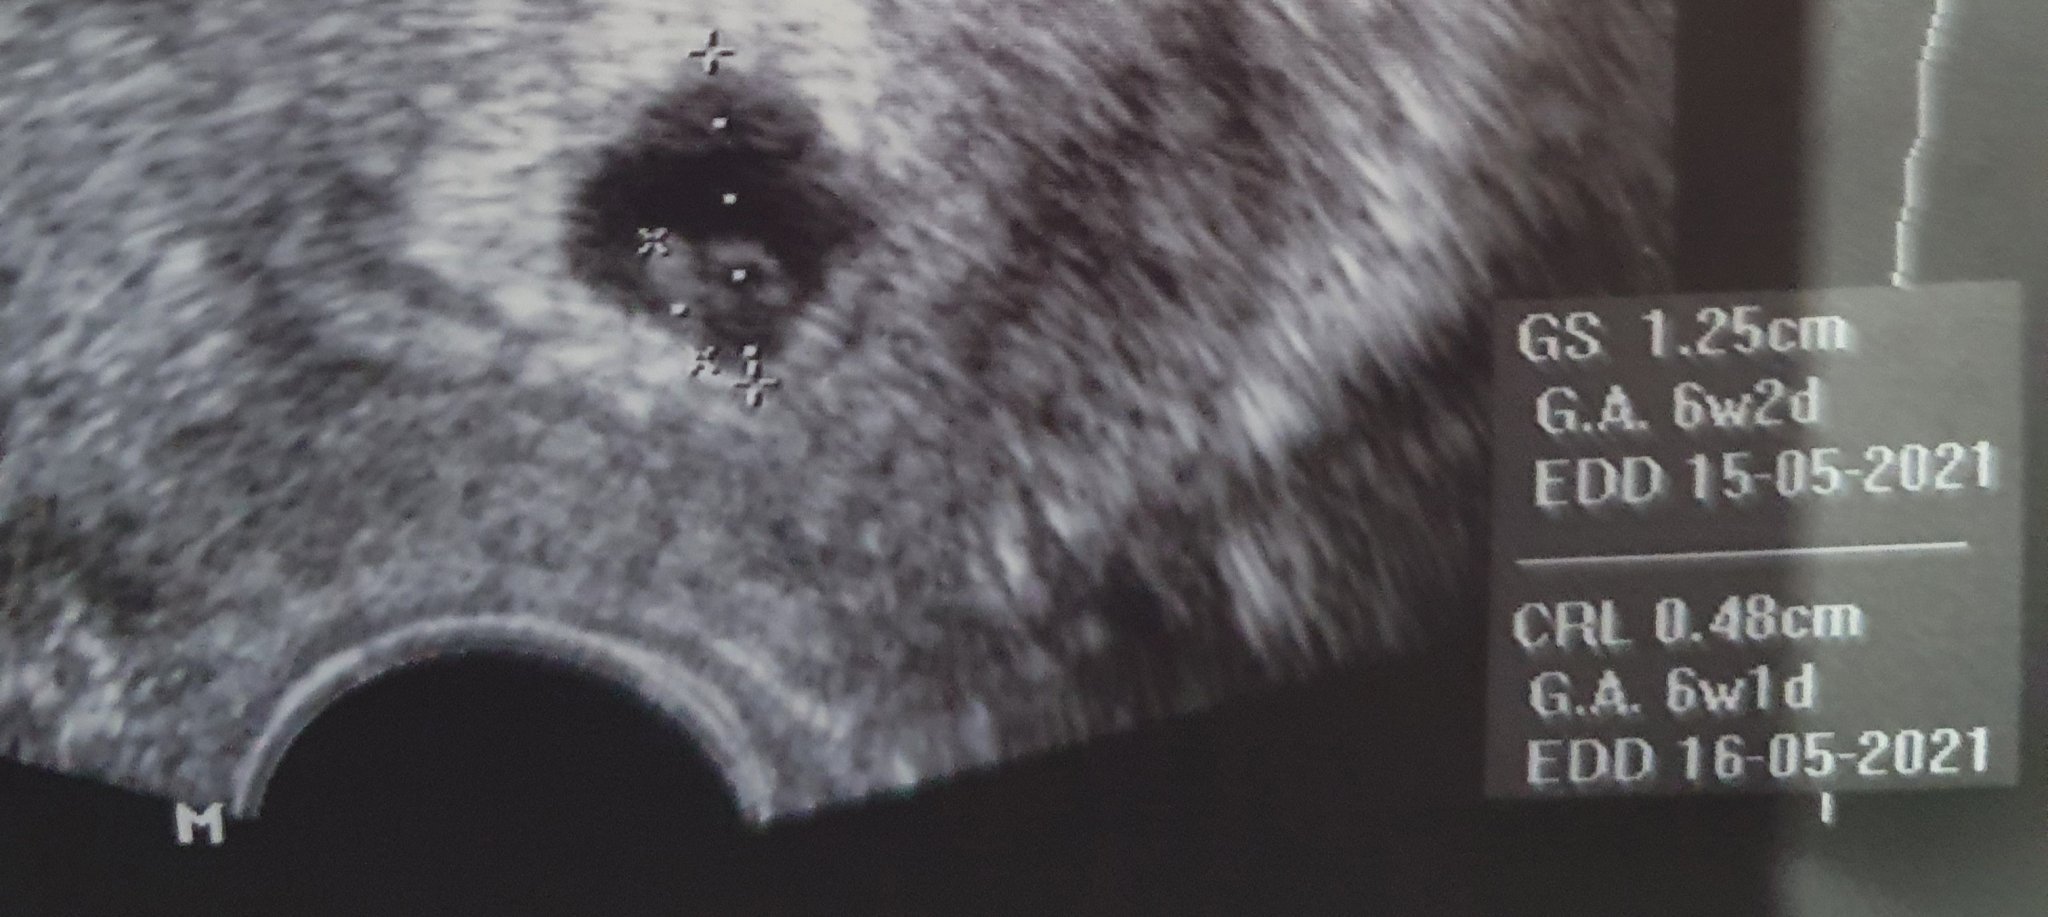

Ох дано имаме късмет Sad виж моите снимки от 2 седмици разлика в преглените

Не мога да се примиря че нещо не е наред Sad Sad